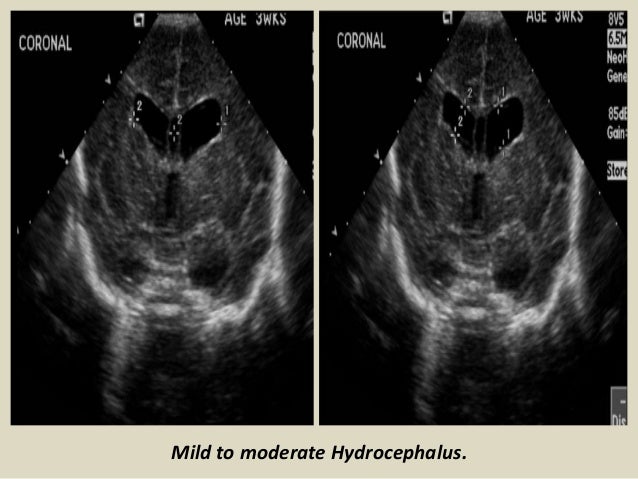

40. 40. Hydrocephalus. Obstructive: non-communicating). Most common. CSF cannot enter subarachnoid space Aqueductal stenosis, Chiari Malformation, Dandy-Walker. Non-obstructive: communicating). Impaired CSF resorption. Infection, hemorrhage, congenital absence arachnoid villi. Ex Vacuo: Loss of brain parenchyma lead to increase CSF spaces.

41. 41. Mild to moderate Hydrocephalus.

42. 42. Mild Hydrocephalus. Moderate to marked Hydrocephalus.

43. 43. Coronal section - Hydrocephalus with little ventricular dilation (blue stars). Coronal section – Large hydrocephalus (blue star).